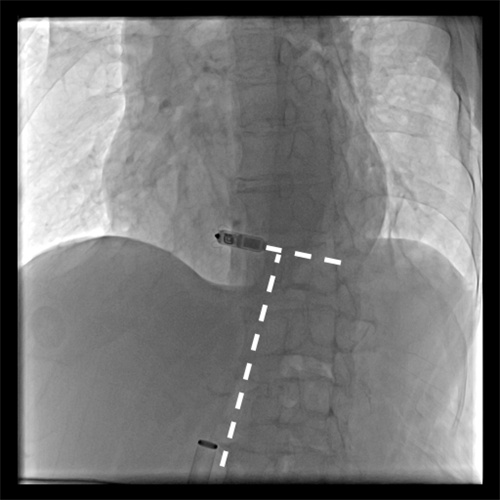

无导线起搏器脱落

近日,湖南省人民医院集团澧县人民医院利用介入技术成功处理了一位八旬老太的罕见“心”事。这位八旬老太因反复出现心慌来到医院。经检查发现是植入的无导线起搏器出现移位,并发频繁地异位起搏,并且脱落的起搏器在心脏里到处乱串,严重威胁到老人生命安全。湖南省人民医院派驻澧县人民医院的颜鹏副院长接手后,率领当地介入血管外科和心内科紧急制定处理方案。在没有可借鉴经验的困难情况下 ,创新性地采用单通道双圈套器技术,仅仅通过腿部米粒大小的穿刺针道,成功取出了这个脱落的起搏器,该患者也得到了顺利救治康复出院。查阅相关文献,这也属于国际上罕见的成功处置案例。